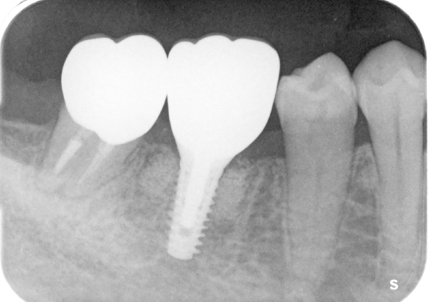

5.インプラント埋入(2021年6月)

※ 初期固定35N/cm確認する

8.補綴物完成(埋入後5か月)